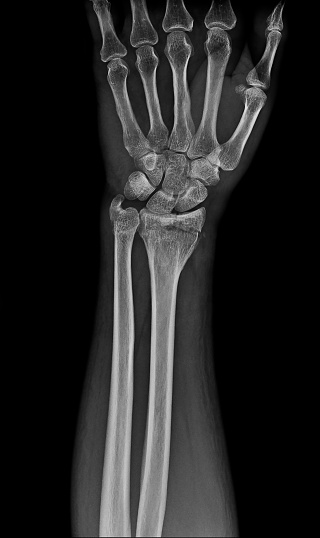

- 영상 검사 : X-ray, MRI, 초음파 등을 통해 손목의 구조적 문제를 확인합니다. 이러한 검사는 손목의 뼈, 인대, 힘줄의 상태를 평가하는 데 도움을 줍니다.